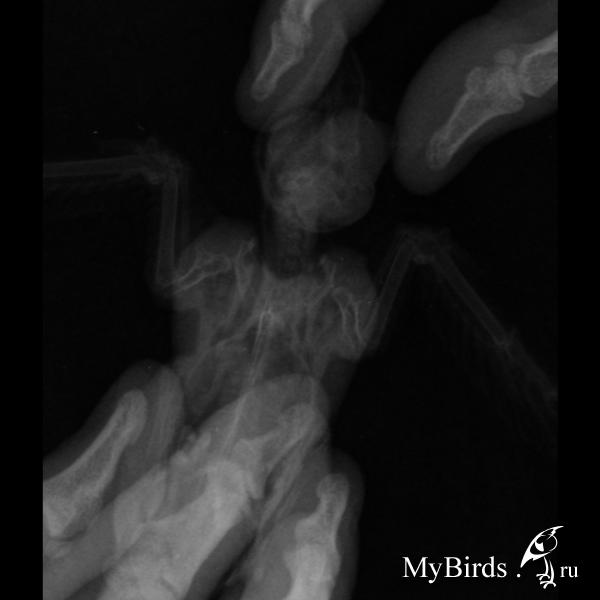

Читая темы этого сайта,дошло,что нужен рентген.На следующий день рентген сделан,вывод айболита тот же.

снимки с очень неудачного ракурса. снимать надо строго сверху, чтобы птицу было видно по оси симметрии. но и так видно, что одно плечо ниже другого.

извините, птице не помочь - плечевой сустав разрушен. она не полетит.